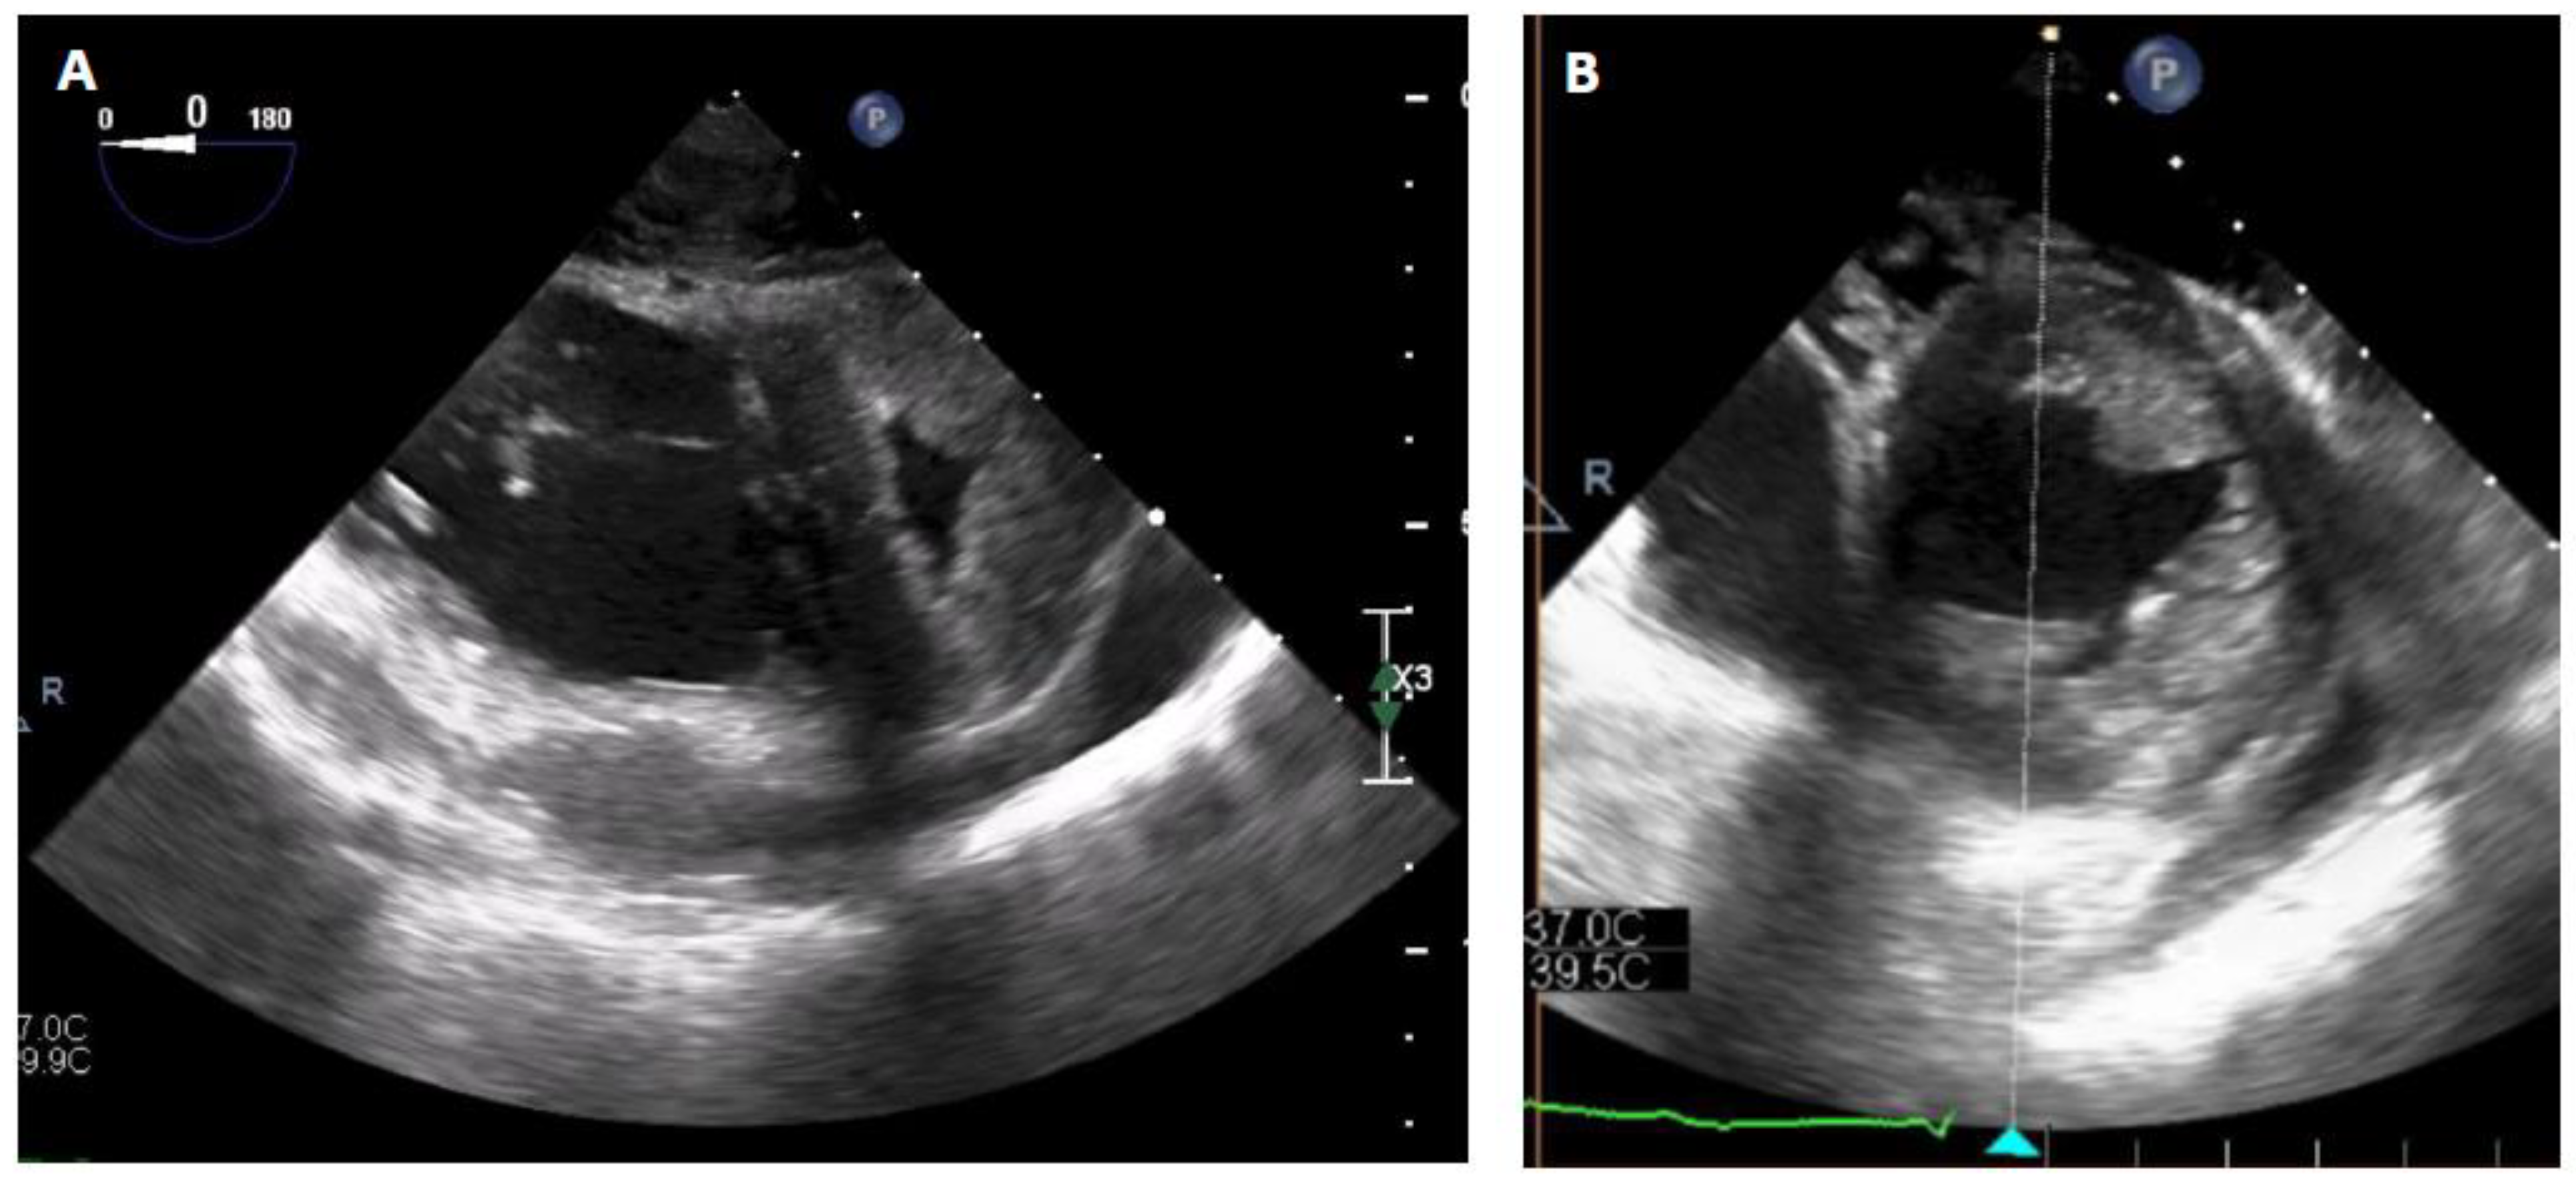

Figure 3. Intraoperative TOE images before VA-ECMO explantation (Panel A) and under ProtekDuo support only (Panel B). The right ventricle was suitable unloaded by the RVAD, while the left ventricle resumed a circular shape with complete regression of the D-shaped sign.

When the patient stabilized and organ function was restored, sedation was stopped, allowing neurological evaluation. Awakening occurred on postoperative Day 4, without any neurological sequelae, and the patient was extubated. Levosimendan was initiated on Day 10, and fluid depletion was achieved through diuretic administration. Nonetheless, the patient could not be weaned off VA-ECMO due to an akinetic and nonrecruitable right ventricle, despite inotropic support. It was decided to wait further on MCS. The patient was conscious, calm, and cooperative but remained bedridden because of the femoro-femoral VA-ECMO. After two weeks, the patient still could not be weaned off VA-ECMO. Indeed, below two liters per minute of blood flow, the patient showed both macrocirculatory and microcirculatory signs of ARF. The mean arterial pressure dropped, the central venous pressure (CVP) increased up to 25 mmHg, the SvO2 dropped from 60 to 30%, the lactate level increased up to 4 mmol/l, and the patient became oliguric. The TOE exam showed a severely dilated and akinetic RV (TAPSE = 4mm, S’ VD 2.3 cm/s, FAC RV = 10%), a small LV size with a preserved function and a LVOT VTI 10 cm/s. Due to her age and an INTERMACS 1 profile, the patient was not eligible, in our country, for a heart transplant or a definitive RVAD implantation (Heartmate III, modified insertion for the right ventricle). Faced with the prospect of prolonged weaning and no other therapeutic alternatives, VA-ECMO was switched to a temporary percutaneous RVAD by implanting a ProtekDuo cannula through the right internal jugular route (Figure 2). A CentriMagTM centrifugal pump (Abbott, Chicago, USA) without an oxygenator was connected to the cannula with an initial flow rate of 4 liters per minute. After a few minutes, the VA-ECMO components could be removed without any vasopressor support. After the initiation of the RVAD, intraoperative TEE showed a reconfiguration of the ventricles. The right ventricle was suitable unloaded by the RVAD, while the left ventricle resumed a circular shape with complete regression of the D-shaped sign (Figure 3). The hemodynamic tolerance of the RVAD was very good (lactate levels < 2 mmol/L, SvO2 > 60%, normal renal and hepatic function). The day after the implantation, the patient was out of bed, placed in a chair, and began rehabilitation. Slow and gradual weaning was instituted. In fact, during the following three weeks, a gradual reduction in the flow rate of the RVAD was carried out at a rate of approximately one liter per week. Interestingly, the serial TTE exam did not show a significant improvement in RV contractile function, but as the pulmonary pressure, pulmonary resistance and LVEDP remained low, the patient’s hemodynamics adapted and showed physiological similarities with a Fontan circulation. During gradual weaning, the renal and hepatic function was monitored daily (creatinine, BUN, AST, ALT, Bilirubine and Factor V levels) and we did not observe any biological signs of congestion or organ dysfunction. Finally, the patient could undergo explantation after 3 weeks of RVAD support. Closed monitoring for 5 additional days was carried out in the ICU. Right ventricular systolic function remained poor (three-dimensional RV ejection fraction (RVEF) = 26%, RV fractional area change (FAC) = 21%, severely reduced longitudinal function with global akinesia except for the apical segments of the anterior and lateral wall) but was well tolerated. CVP remained below 15 mmHg, SvO2 was above 60% with normal lactate levels, and renal and hepatic functions remained stable. Anticoagulation therapy was empirically initiated to prevent thromboembolic events, as the patient would likely not survive any abrupt increase in RV afterload. Diuretics and antihypertensive treatments were continued to maintain a low LVEDP. To be noted, during mechanical circulatory support, the patient did develop only minor ECMO-related complications. Minor bleeding at the canula site were noted after canulation and stopped rapidly after optimization of the coagulation profile. Femoral venous thrombosis (at the site of the cannula) was diagnosed after explantation and treated accordingly. We did not observe any Protekduo-related complications.